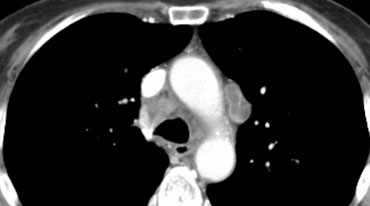

Ví dụ:

Khối u bên phải với di căn hạch N3, bao gồm các trạm trung thất đối bên 4L và 5.

Các hình ảnh này thuộc về hai bệnh nhân khác nhau bị ung thư phổi ở phổi phải.

Hình ảnh

Có các hạch bạch huyết ở phía đối bên.

Nếu các hạch bạch huyết này chứa tế bào ung thư, điều đó có nghĩa là bệnh giai đoạn N3.